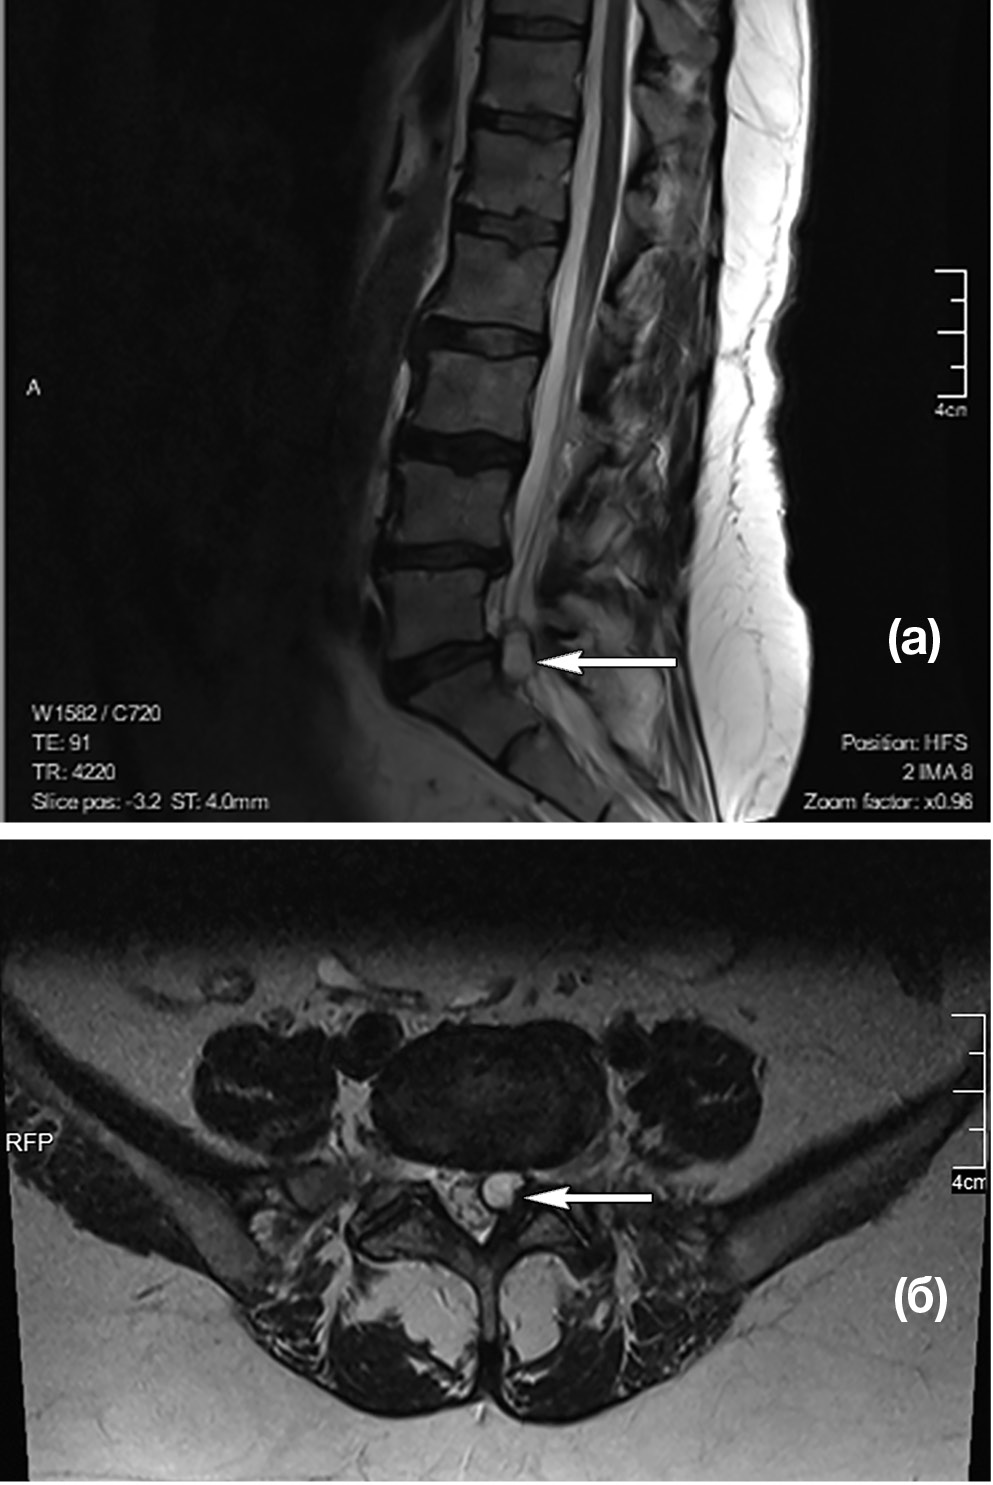

МРТ поясничного отдела позвоночника (рис. 1, 2): дегенеративно-дистрофические изменения пояснично-крестцового отдела позвоночника — 3-й период. Позвоночный канал деформирован на уровне LV-SI слева с сужением резервного эпидурального пространства и стенозированием левых латеральных отделов позвоночного канала на ширину до 0,3 см. Слева в промежутке LV-SI визуализируется образование с ровными четкими контурами, гиперинтенсивного сигнала в Т2и гипоинтенсивного сигнала в Т1-режимах, размером 14×8×8,5 мм. Прослеживается связь образования с дугоотростчатым суставом. Киста пролабирует из полости сустава в позвоночный канал по левому боковому карману, приводя к стенозу и компрессии спинномозговых корешков на уровне LV-SI.

Рис. 1. Пациентка C.: МР-томограмма поясничного отдела позвоночника в T2-режиме в сагиттальной (а) и аксиальной (б) проекциях. Аксиальная проекция выполнена на уровне диска LV-SI (стрелкой указана периартикулярная фасеточная киста)

Важно отметить, что на фронтальных МРТ-сканах периартикулярная киста компримирует спинномозговой корешок SI. Прослеживается расположение кисты в латеральном канале, где отмечается щелевидная полость, которая сообщается с полостью фасеточного сустава.